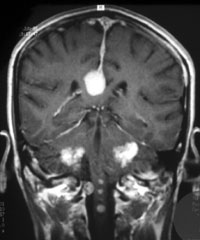

Wie schon erwähnt findet man bei 90 % der Betroffenen bei einer Kernspintomographie des Schädels ein beidseitiges Akustikusneurinom.

Akustikusneurinome sind die häufigsten gutartigen Tumoren der lateralen Schädelbasis. Über zwei Drittel der im Kleinhirnbrückenwinkel gelegenen Schwannome entfallen auf die Vestibularisschwannome.

Beidseitige Vestibularisschwannome sind das Hauptmerkmal der Neurofibromatose Typ 2 (NF2) und aufgrund der Kriterien des National Institutes of Health (NIH) gelten sie als das entscheidende Kriterium für diese Erkrankung.

Die Bezeichnung Akustikusneurinom (AN oder AKN) ist historisch begründet. Korrekter ist allerdings die Bezeichnung Vestibularisschwannom, da der Ursprung der Tumoren in den Schwannschen Hüllzellen (beteiligt am Aufbau markhaltiger und markloser Nervenfasern) des vestibulären Anteiles des Nervus vestibulocochlearis (8. Hirnnerven) liegt. Dieser vermittelt Informationen vom Gleichgewichtsorgan an das Gehirn, während der cochleäre Anteil die Hörimpulse leitet. Der 8. Hirnnerv verläuft zusammen mit dem Nerv für Gesichtsbewegungen (7. Hirnnerv, nervus facialis) vom Hirnstamm in den inneren Gehörgang (ein kleiner knöcherner Kanal im Felsenbein) bis zum Hör- und Gleichgewichtsorgan.

Meist beginnt das Wachstum des Tumors im inneren Gehörgang. Mit zunehmendem Wachstum dehnt sich der Tumor dann schließlich bis in den Kleinhirnbrückenwinkel aus. (Kleinhirnbrückenwinkel ist eine Beschreibung für den Raum zwischen Hirnstamm und Kleinhirn im Bereich der hinteren Schädelgrube).